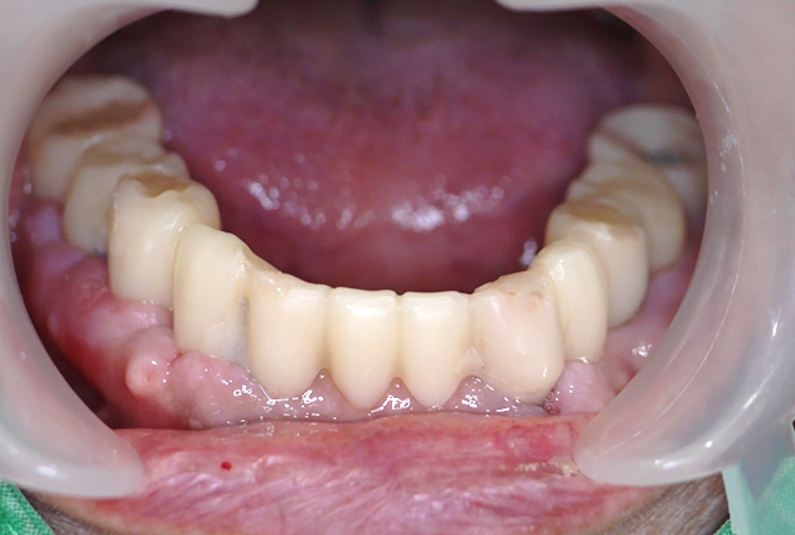

張阿姨的轉變:

穩固舒適: 正式假牙牢牢固定在植體上,比活動假牙穩固百倍,毫無異物感。

咀嚼有力: 困擾已久的進食問題徹底解決,終於能好好享用美食,啃蘋果、吃排骨不再是奢望。

口氣清新: 固定假牙易於清潔,徹底解決了假牙異味問題,重拾社交自信。

生活品質飛躍: 告別假牙煩惱,笑容更燦爛,享受晚年美食樂趣。